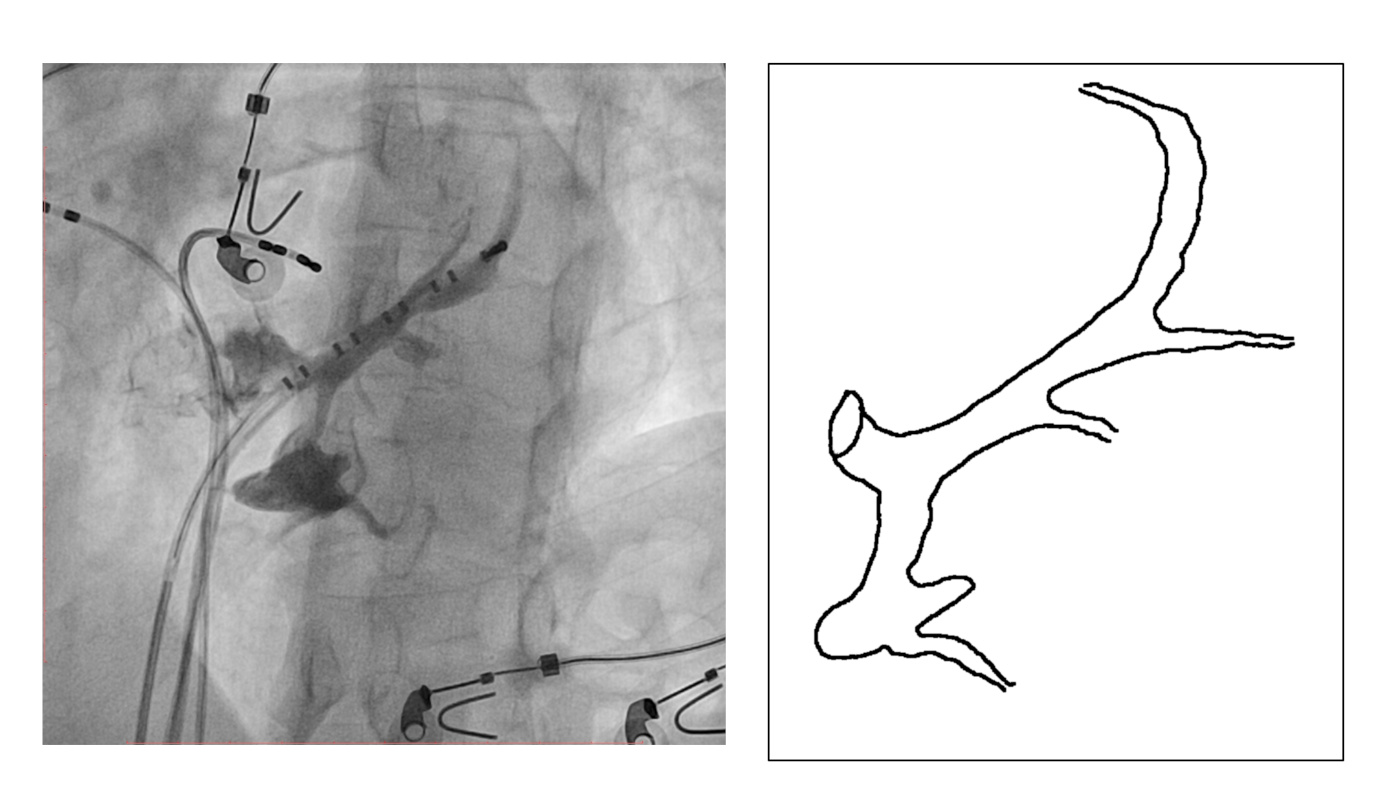

CS diverticulum

ecg.jpg

Mapping in diverticulum

diverticulum.jpg

med_lat_div.jpg

signals.jpg

Mapping in diverticulum - CSE potential most important

div_schematic.jpg

Selvaraj RJ et al. Radiofrequency ablation of posteroseptal accessory pathways associated with coronary sinus diverticula. J Interv Card Electrophysiol. 2016 Nov;47(2):253-259. doi: 10.1007/s10840-016-0113-x.

In absence of diverticulum, map along tributaries

no_diverticulum.jpg